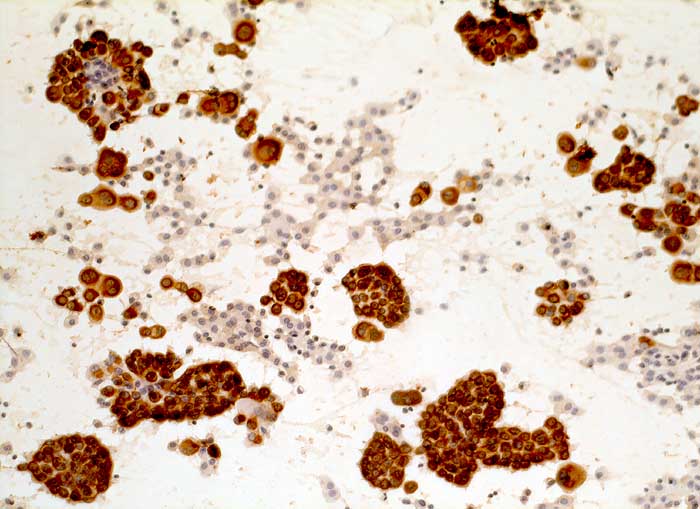

Pleurapunktat: Die rundlichen und papilliformen Tumorzellverbände sind deutlich positiv für den Panzytokeratinmarker Lu-5. Makrophagen und Lymphozyten sind negativ.

Immunzytochemisch sind die im Vorbericht beschriebenen Tumorzellen eindeutig positiv für Lu-5, Calretinin und Vimentin, dagegen komplett negativ für Ber-EP4 und CEA. Diese Konstellation ist sehr typisch für ein malignes Pleuramesotheliom.

Lu5 Panzytokeratin

200